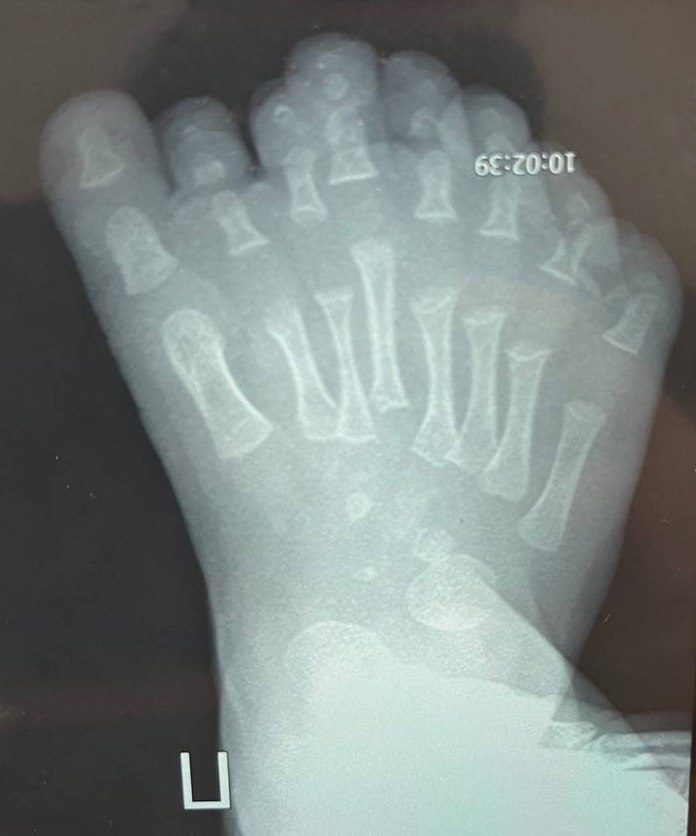

Иркутские врачи удалили лишние пальцы у малыша

Ребенок родился с восьмью пальцами на ноге.

Такая патология называется полидактилией, она приводит к нарушению развития стопы. Чтобы избежать негативных последствий, врачи Ивано-Матренинской детской клинической больницы провели сложную операцию.

По словам врача травматолога ортопеда Ильи Зеленина, особенность полидактилии у пациента заключалась в том, что было увеличено не только количество фаланг пальцев, но и количество плюсневых костей.

Операция была сложная, перевязки проводят каждый день. Малыш останется под наблюдением врачей ещё долго. Сейчас ребенку семь месяцев, и как раз летом он сможет сделать свои первые шаги.

— К году стопа должна полностью зажить, кости — перестроиться и встать на свое определенное природой место, — говорит Илья Зеленин.